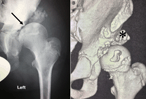

A 10-year follow-up of asymptomatic Charcot hip joints caused by CIPA syndrome (congenital insensitivity to pain with anhidrosis) with failure of any surgical reconstructive treatment

Ioannis Delniotis and Benedikt Leidinger

Journal of Surgical Case Reports, Volume 2019, Issue 5, May 2019, rjz154, https://doi.org/10.1093/jscr/rjz154